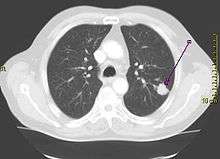

| A chest X-ray showing a tumor in the lung (marked by arrow) | |